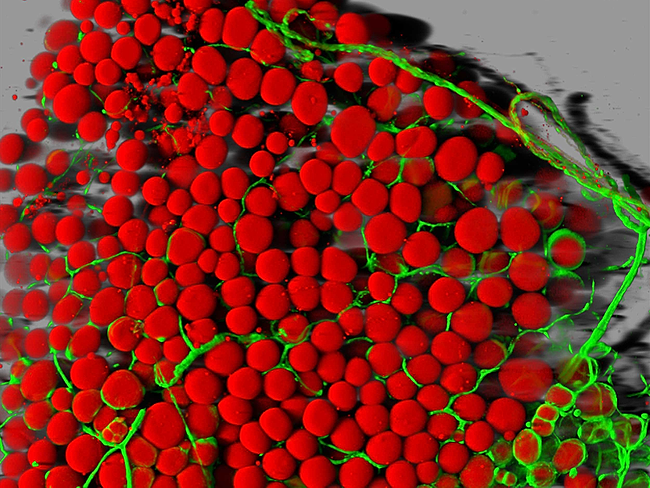

• Cancer and blood cells

Hematopoietic stem cell research points to leukemia’s early roots

BioWorld Science

Hematopoietic stem cell (HSC) research over the past century has shown that leukemia may be driven by an invisible hand of inflammation. The bone marrow and...